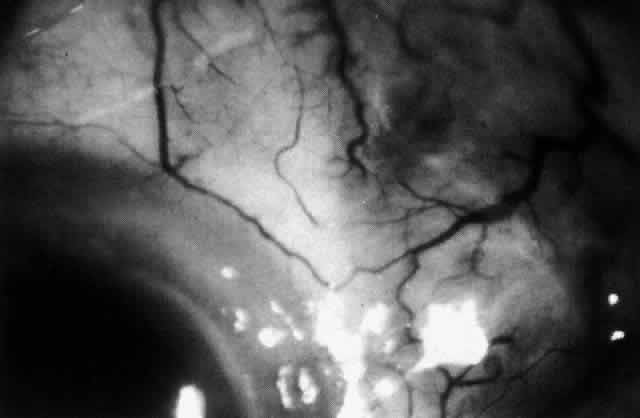

The characteristic features of necrotizing scleritis on fluorescein angiography are hypoperfusion and, eventually, nonperfusion of the vascular networks (Figs. 40 through 43).26 The initial changes are on the venous side of the capillary network; the transit time of the dye increases even if the eye is red and congested. If the disease process persists or has been present for a long time, thrombosis and permanent vaso-occlusive changes occur. These vessels (or the occluded capillary network) are bypassed by the opening of anastomotic channels. New vessels in a granuloma give rise to deep intrascleral leakage of dye (see Fig. 43). Conjunctival and episcleral involvement by the destructive change is late but is always preceded by vaso-occlusive changes that can sometimes be detected with use of the red-free light on the slit lamp (Figs. 44 and 45).

Fig. 40. Early necrotizing scleritis. There is characteristic yellow discoloration of the sclera underlying the conjunctiva at a point of necrosis. In this instance a small filament of tissue has penetrated the conjunctiva.

Fig. 41. Late stage of fluorescein angiogram adjacent to the site of necrosis in the same patient as in Figure 40. Although the eye is uniformly congested, the area near the necrosis shows vascular shutdown, whereas the rest of the conjunctiva and episclera is normally perfused.

Fig. 42. Late arterial phase of fluorescein angiogram in a patient with necrotizing scleritis. All the vessels except the main trunk and the vessels around the limbal perforating vessels are occluded and remain unperfused throughout the angiogram.

Fig. 43. Late venous phase of angiogram of a patient with necrotizing scleritis showing late deep leakage from vessels on the surface of the sclera and leakage of the capillary network at the limbus and the vessels draining it, together with poor or absent perfusion of the remaining vessels.